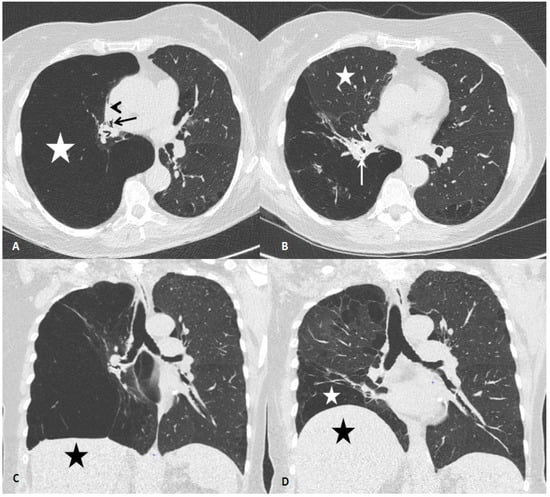

2. Case Report